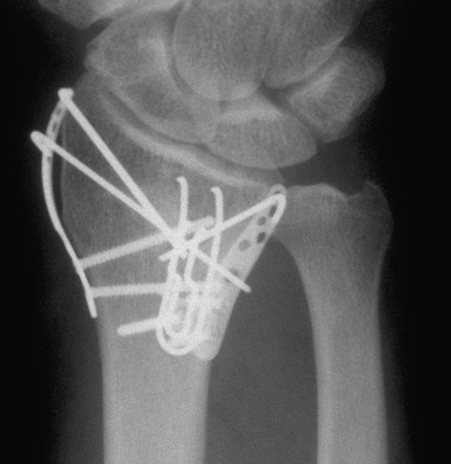

Case 2 Postop